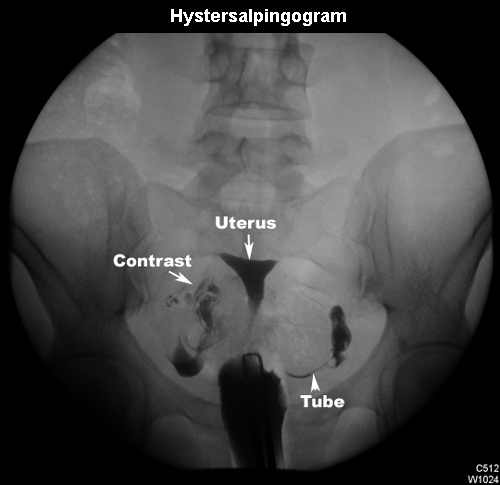

Hysterosalpingogram |

|